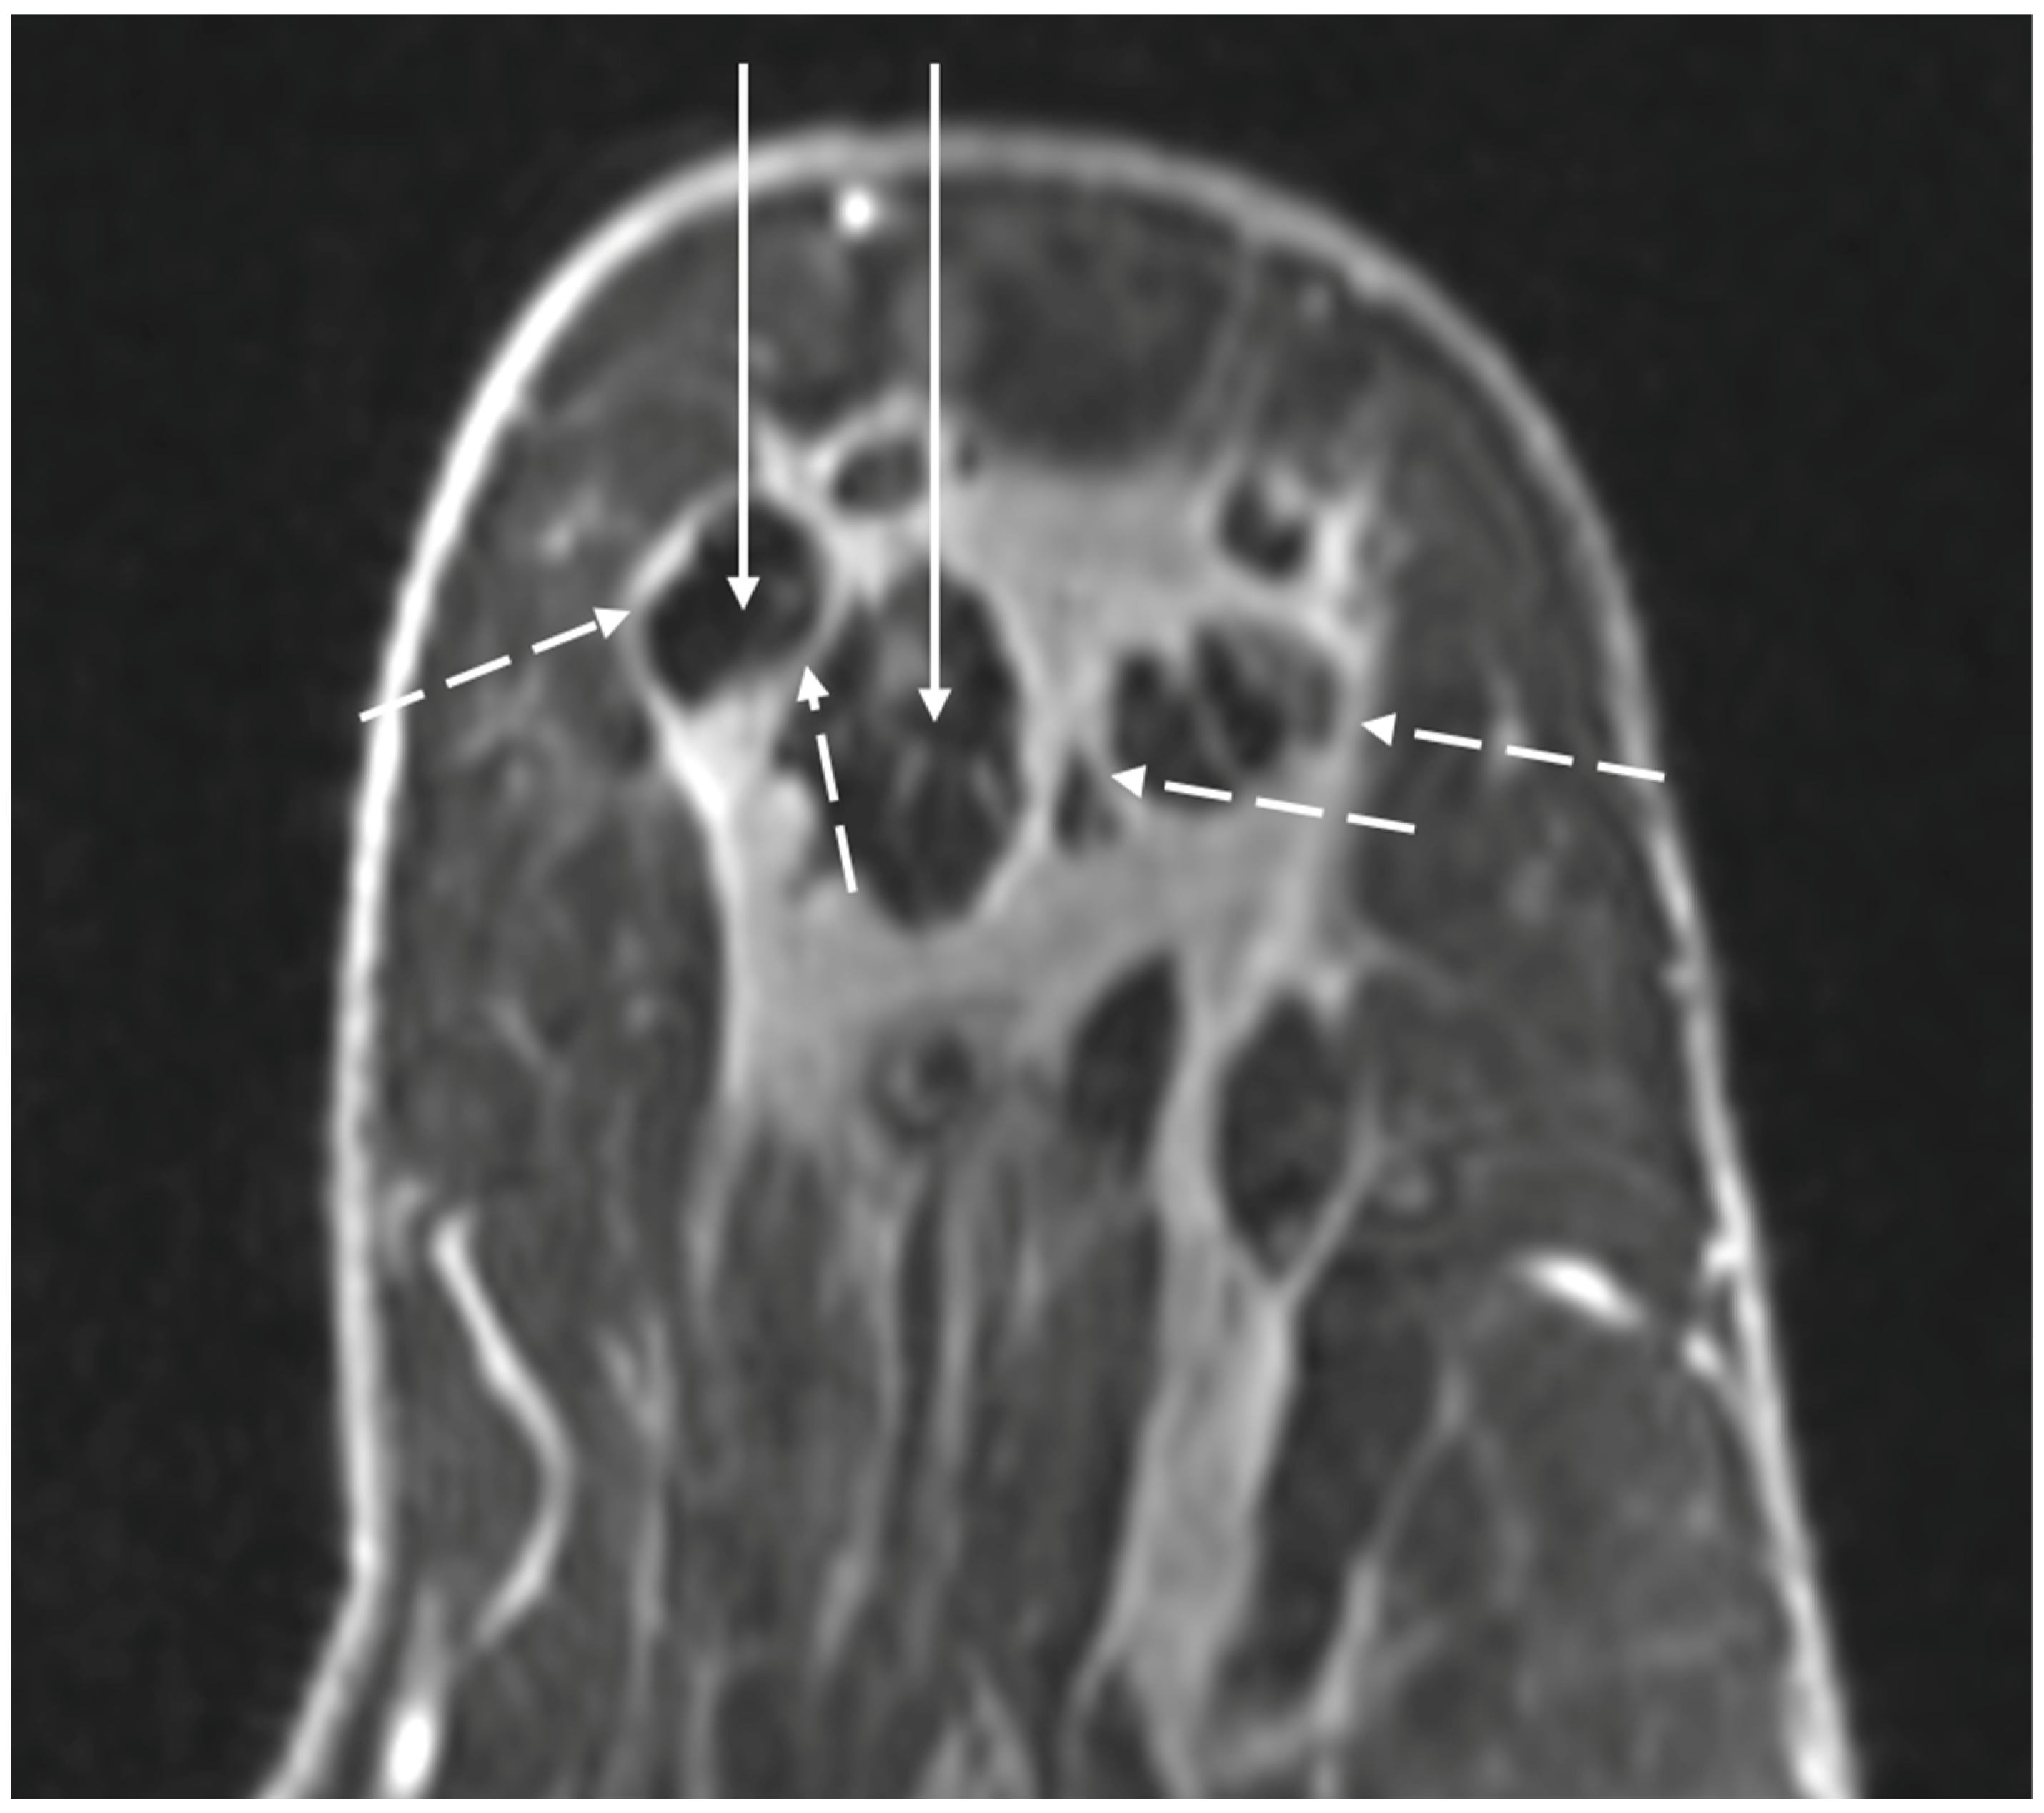

Contrast-Enhanced Breast MRI. Contrast enhanced breast MRI improves assessment of disease extent, including detection of spiculations, multifocal, multicentric, or contralateral disease, which might impact eligibility for cryoablation or alter the overall treatment plan (Figure 4). Contrast-enhanced breast MRI has the added value of permitting 3-D image reconstruction to permit viewing of the tumor from various angles for a more comprehensive assessment of tumor shape and size. Breast MRI for cancer evaluation requires the use of an intravenous contrast containing gadolinium that can be safely administered with minimal short-term and long-term risks. However, patients unwilling or unable to receive gadolinium might be able to access dedicated breast-only diffusion weighted MRI, which has limited availability in the U.S.

Figure 4.

Contrast-enhanced breast MRI image showing multifocal disease indicated by mass-like enhancement of dominant mass (indicated by single arrow and encircled with hash marks) as well as mass-like enhancement of a second focus of disease (indicated by double arrows and encircled with hash marks). The second focus was mammographically-occult.